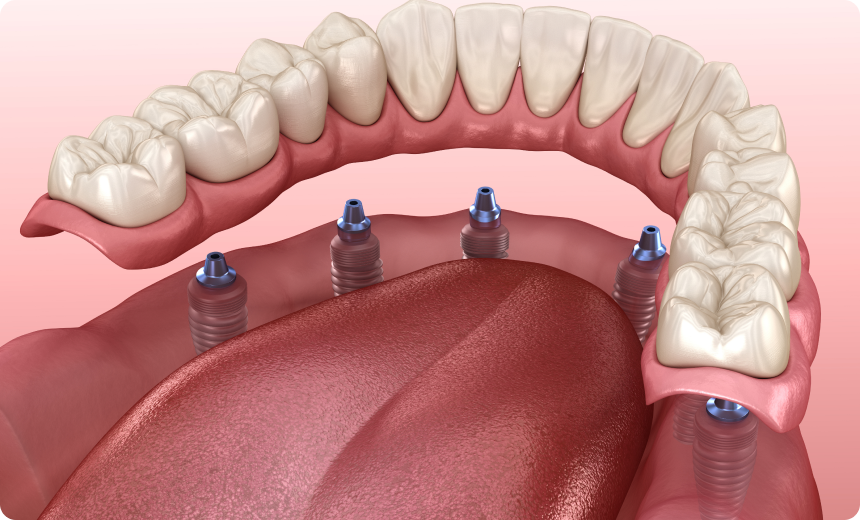

Le concept All-on-6 est une technique de réhabilitation dentaire qui consiste à poser une prothèse fixe sur six implants insérés dans la mâchoire. Cette méthode permet de remplacer toutes les dents d’une arcade dentaire lorsqu’elles sont absentes ou irrécupérables.

Le principe repose sur la répartition équilibrée de six implants stratégiquement positionnés dans l’os maxillaire ou mandibulaire. Cette répartition permet de soutenir une prothèse complète, tout en limitant le nombre d’implants nécessaires par rapport à une reconstruction traditionnelle qui en demande souvent plus.

Sous anesthésie locale, les six implants sont insérés dans l’os. Leur position est calculée pour supporter efficacement la future prothèse. La chirurgie dure généralement quelques heures et peut parfois être réalisée en une seule séance.

Une fois l’ostéointégration confirmée, une prothèse fixe définitive est confectionnée sur mesure. Elle est vissée aux implants et permet de retrouver confort et fonctionnalité sur le long terme.

Le All-on-4 repose sur la pose de quatre implants pour soutenir une arcade complète. Le All-on-6 en utilise deux de plus, ce qui assure une répartition plus homogène des forces masticatoires. Cette différence rend la solution All-on-6 particulièrement adaptée aux patients ayant une densité osseuse suffisante et recherchant une stabilité renforcée.